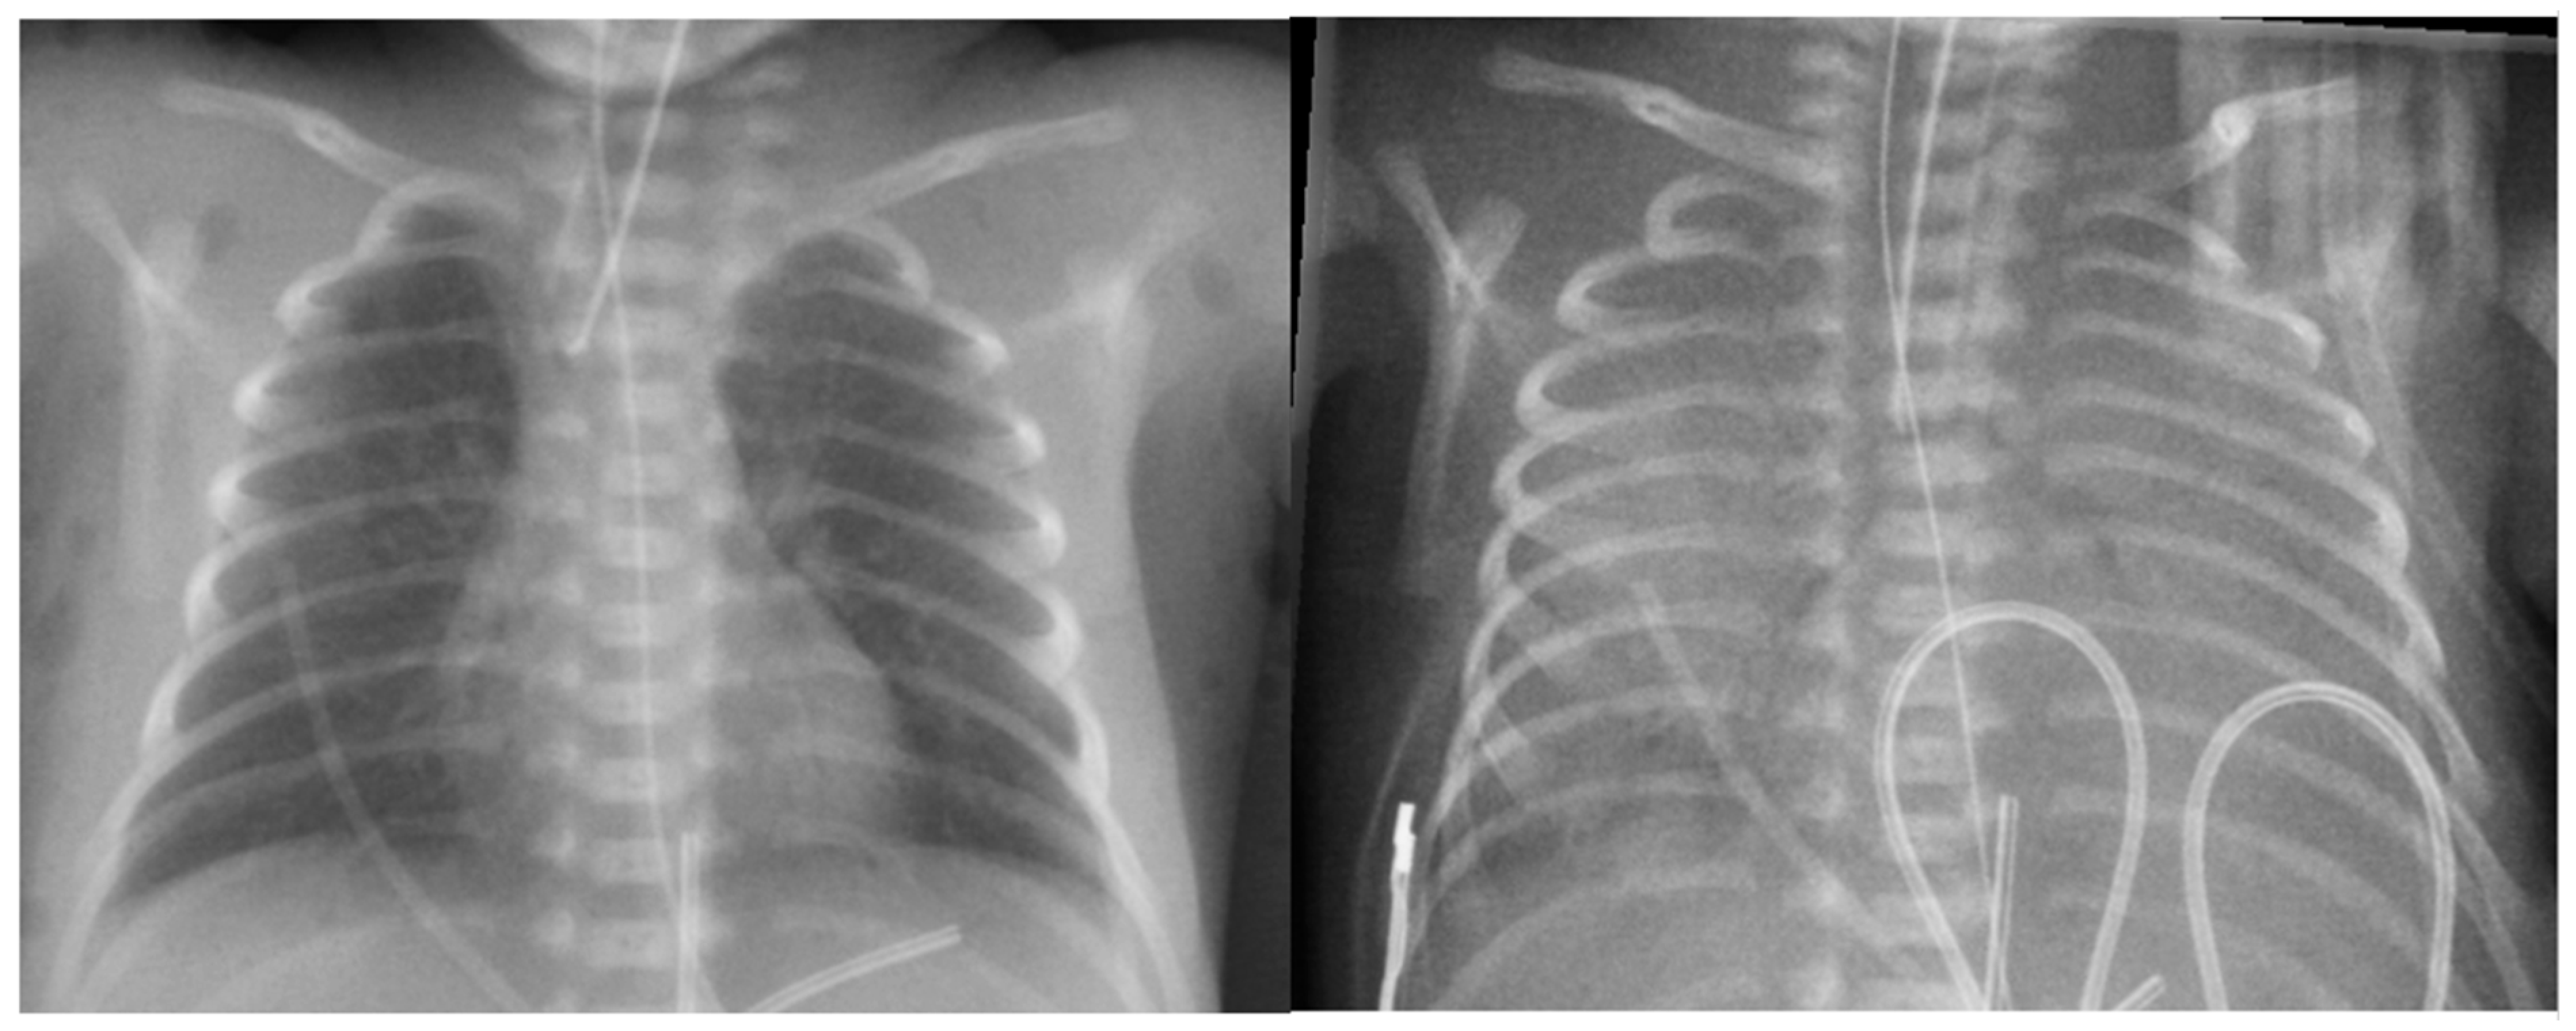

6.3. Radiological Diagnosis